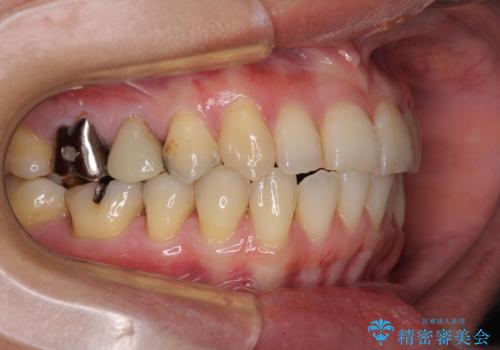

- 前歯のデコボコを気にして来院された患者様です。

上下前歯の先端同士が接触する切端咬合であったため、上顎は歯列を拡大し、下顎はIPR(歯と歯の間を削る)により叢生を解消しながら歯列を小さくすることとしました。

矯正装置にはインビザラインを用いることとしました。

治療途中に前歯に歯髄充血を思わせる痛みが認められたため、無理のない歯の移動と頻繁な経過観察を行いました。

切端咬合はスムーズに解消され、前歯の負担を軽減させることができました。